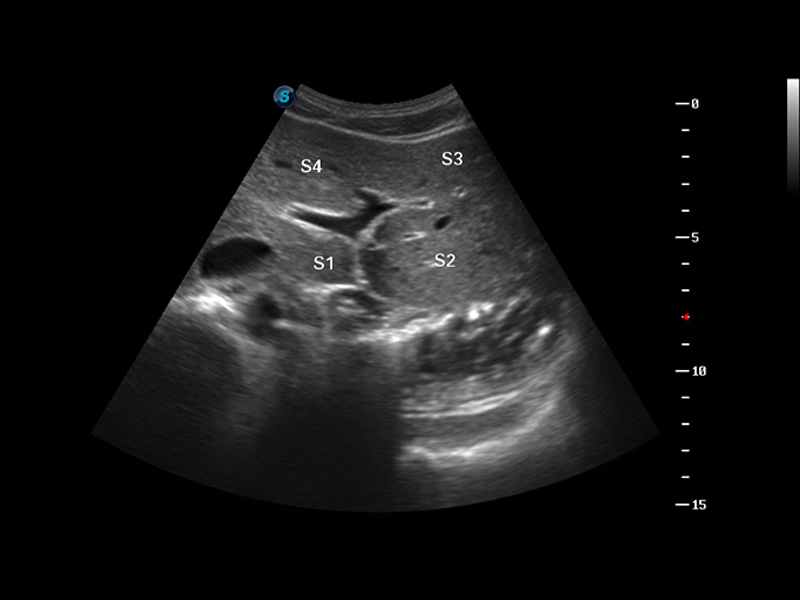

S8 EXP便携式彩色多普勒超声诊断仪是1xBET研发的高端全身应用型便携彩超。高通道的VIS平台融合可视化(Visual)、智能化(Intelligent)和人性化(Smart)的特点,配以1xBET自主研发生产的探头大家族,使您能够快速、准确的获得病人信息,提高工作效率的同时减轻疲劳。

μ-Scan微米成像

谐波成像

空间复合成像

3D/4D成像